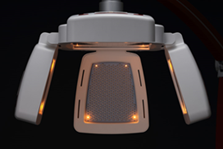

当院では、アデランス社製のLED治療機「N-LED 5000 DK」を導入しています。

当院で導入しているは、毛髪研究で知られるアデランス社が開発した医療用LED機器です。

当院の「N-LED 5000 DK」は、のLEDに加え、プラズマクラスター機能を搭載しています。

当院のLED治療機「N-LED 5000 DK」は、頭皮と顔を同時に照射できる設計になっています。